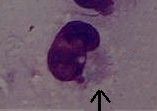

| Chlamydia |

Giemsa stain |

blue-purple inclusion bodies